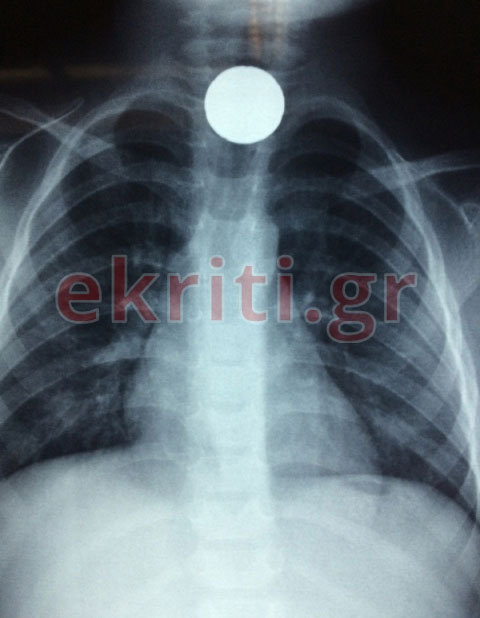

Είχαμε, σύμφωνα με την ιατρική γνωμάτευση λοιπόν την αφαιρεση του ξενου σώματος (20 cents) απο το ανώτερο τμήμα του οισοφάγου. Το ξένο σωμα είναι το στρογγυλό άσπρο σημείο που φαίνεται στην ακτινογραφία θώρακος.

Για την ιστορία να αναφέρουμε - όπως μπορεί να δει κανείς στην αποκλειστική φωτογραφία με την ακτινογραφία που δημοσιεύει το ekriti.gr - ότι το κέρμα είχε κολλήσει στον οισοφάγο του μικρού παιδιού.